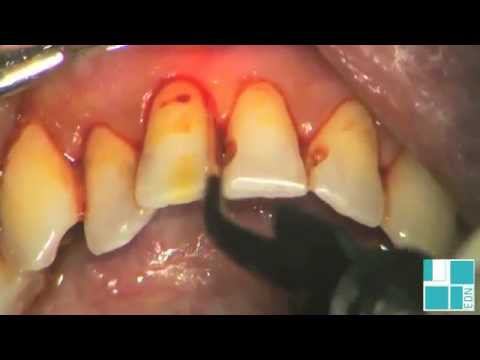

Пародонтология - лечение лазером DEKA.avi